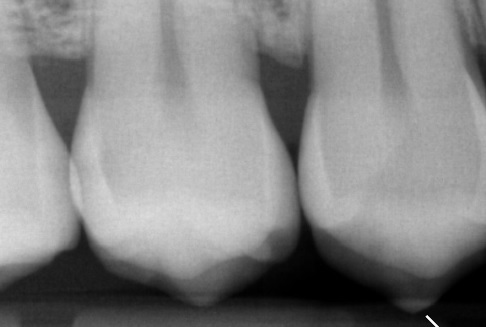

Recent ben ik overgestapt naar een andere tandarts. Bij de nieuwe tandarts blijkt ineens dat ik 6 gaatjes heb, terwijl ik een maand geleden bij mijn vorige tandarts een controle had en daar toen niks aan de hand was. Van deze 6 gaatjes is een vulling die moet worden aangepast en een putje in een kies. Twee andere gaatjes zijn ontstaan onder de vulling. Maar bij de andere twee kiezen kan ik het niet zien. Ik heb hiervan de foto's ontvangen en hij zegt dat daar ook gaatjes in zitten. Maar tussen de twee foto's zie ik geen verschil. Mijn vorige tandarts boort alleen wanneer het echt nodig is en bij de nieuwe krijg ik het gevoel dat die te snel naar de boor krijgt.

Mijn vraag is of er inderdaad gaatjes in deze twee kiezen zitten? En als dit wel het geval is, is het dan nodig om gelijk te boren aangezien er geen verandering is in de afgelopen anderhalf/twee jaar. De eerste foto is ongeveer 1,5/2 jaar geleden gemaakt en andere een week geleden.

Recent ben ik overgestapt naar een andere tandarts. Bij de nieuwe tandarts blijkt ineens dat ik 6 gaatjes heb, terwijl ik een maand geleden bij mijn vorige tandarts een controle had en daar toen niks aan de hand was. Van deze 6 gaatjes is een vulling die moet worden aangepast en een putje in een kies. Twee andere gaatjes zijn ontstaan onder de vulling. Maar bij de andere twee kiezen kan ik het niet zien. Ik heb hiervan de foto's ontvangen en hij zegt dat daar ook gaatjes in zitten. Maar tussen de twee foto's zie ik geen verschil. Mijn vorige tandarts boort alleen wanneer het echt nodig is en bij de nieuwe krijg ik het gevoel dat die te snel naar de boor krijgt.

Mijn vraag is of er inderdaad gaatjes in deze twee kiezen zitten? En als dit wel het geval is, is het dan nodig om gelijk te boren aangezien er geen verandering is in de afgelopen anderhalf/twee jaar. De eerste foto is ongeveer 1,5/2 jaar geleden gemaakt en andere een week geleden.